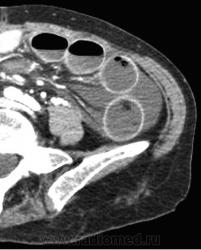

-свободная жидкость между расширенными петлями кишечника, зачастую в виде пикантной детали женского туалета-трусиков танга, поэтому в многих источниках описывается как признак "танга" (tanga sign).

-свободная жидкость в брыжеечных карманах

-свободная жидкость в брюшной полости.

Примеры скопления жидкости между петлями кишечника (танга) и в карманах брыжейки, при декомпенсированной форме.